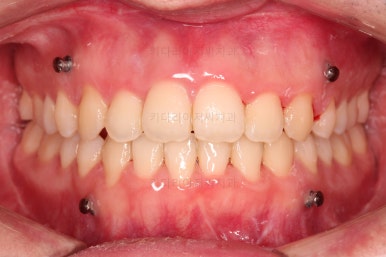

초진 시 입안의 모습입니다.

교합이 많이 안좋습니다.

위아랫니가 서로 엇갈려 가며 지그재그로 껴 들어가야 어금니 맞물림이 생기는데요.

이번 환자분은 아랫니, 아래턱이 전반적으로 앞으로 나와 있어서 교합이 전혀 안되고 있는 상태였습니다.